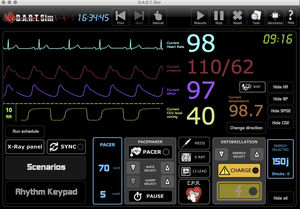

... El software Simulador de ECG DART Sim sólo está disponible para descarga en ordenador. Se requiere Windows XP o MacOSX o un sistema operativo posterior. Cada compra incluye 2 licencias del software DART Sim, para que ...

DART Sim ECG Simulator